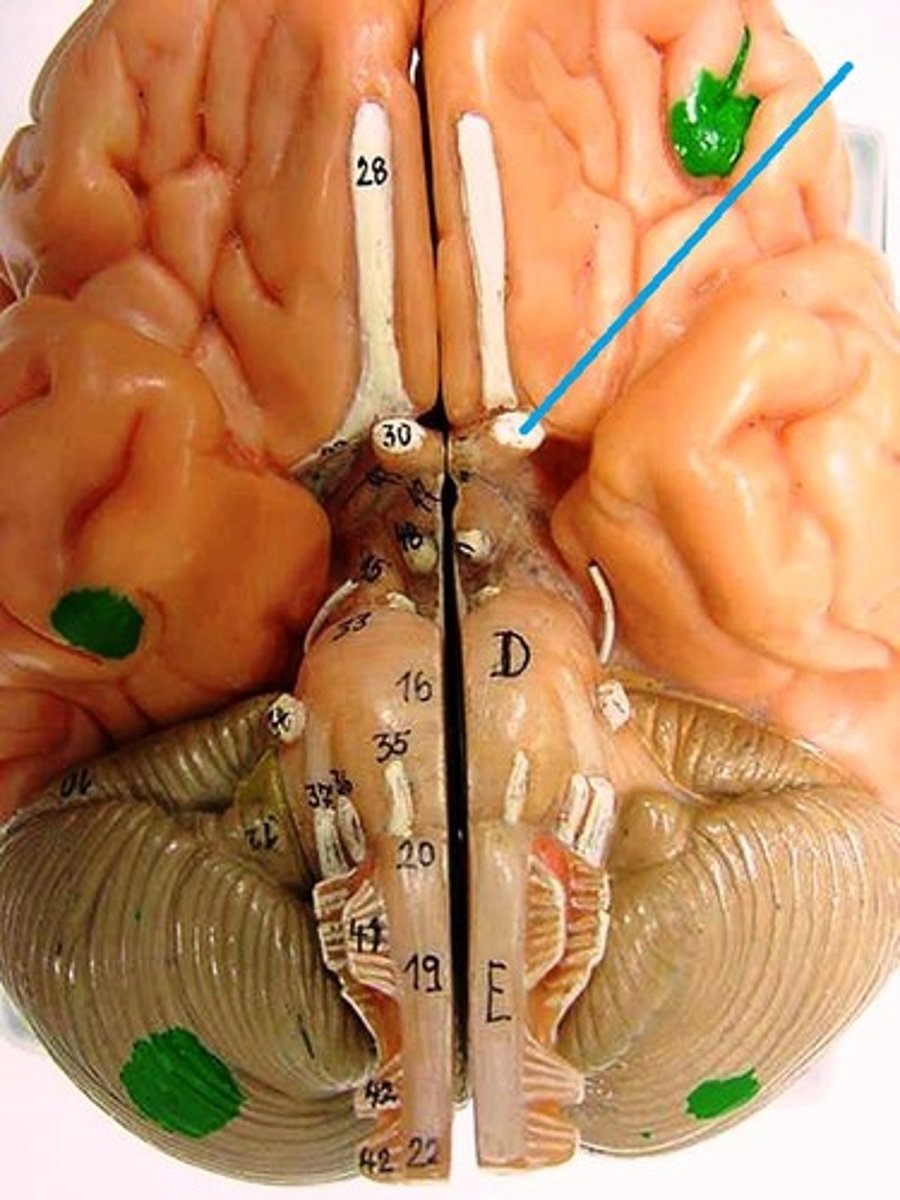

central sulcus

lateral sulcus

transverse fissure

precentral gyrus

postcentral gyrus

cingulate gyrus

longitudinal fissure

corpus callosum

septum pellucidum

optic chiasm

hippocampus

frontal lobe

temporal lobe

parietal lobe

occipital lobe

Broca's area

Prefrontal cortex

Premotor cortex

Wernicke's area

Primary visual cortex

Primary auditory cortex

Amygdala